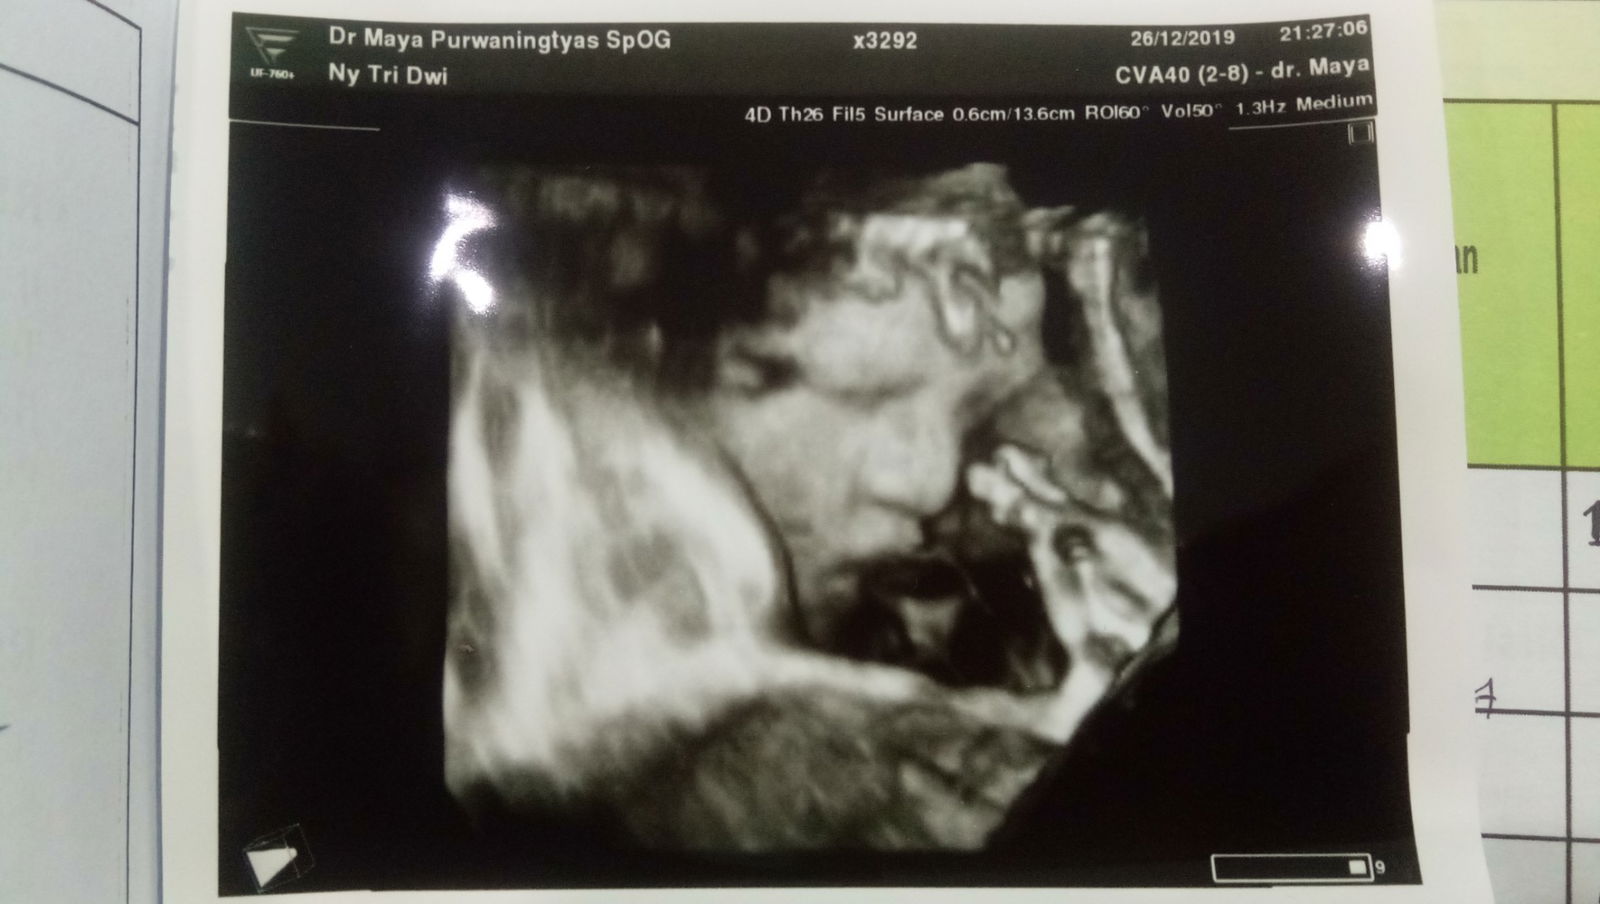

mamanya cinta

babygirl